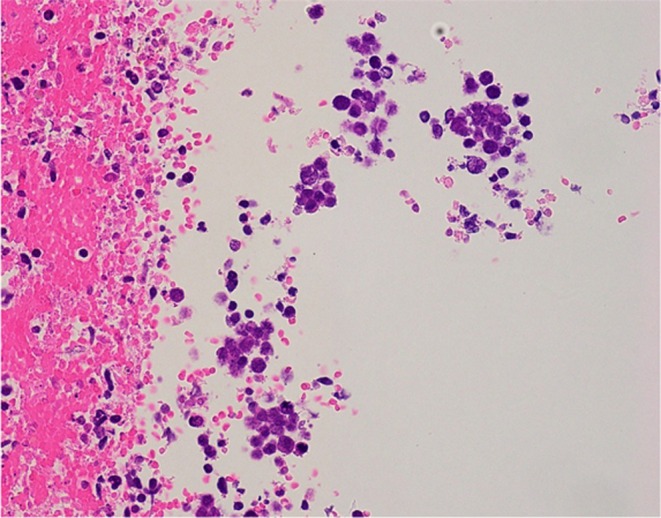

Case presentation: An 80-year-old male with no psychiatric history presented with flu-like symptoms, followed by the acute onset of neuropsychiatric symptoms, including pressured speech, agitation, memory impairment, and abnormal behavior. Autoimmune encephalitis was suspected due to mildly elevated cerebrospinal fluid (CSF) white cell count and a mass in the right upper lung detected by whole-body computed tomography (CT) on the first day of hospitalization. High-dose intravenous corticosteroids were administered on Day 1, resulting in prompt and sustained improvement in symptoms. CSF was later confirmed positive for anti-NMDAR antibodies, and a bronchoscopy biopsy of the pulmonary mass diagnosed SCLC. The patient recovered without neurological deficits and was discharged in stable condition on hospital Day 30.